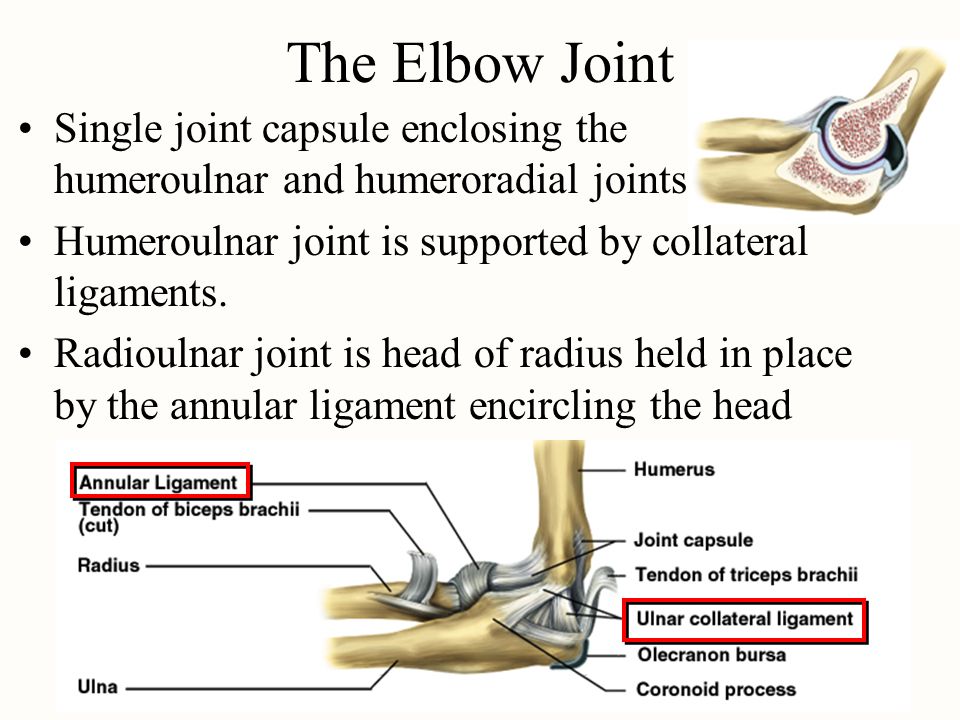

TOPIC: BODY MOVEMENT AS MACHINE

OBJECTIVE: At the end of the lesson, the students should be able to:

1. Describe the movement of the elbow.

2. State the functions of the parts of a joint

CONTENT:

Movement at the elbow is controlled by two antagonistic muscles, the bicep muscle and the tricep muscle.

To lift the lower forelimb, the bicep muscle contracts and the tricep muscle relaxes. To lower forelimb, the bicep muscle relaxes while the tricep muscle contracts.

Parts of a joint Functions

Cartilage It serves as a shock absorber when the joint is under stress.

Synovial fluid - It lubricates the joint and allows for free movement.

Capsule - Wraps up and protects the inner delicate parts of the joint.

Ligament - Holds the joining bones in a ball and socket joint together.

Tendon - Holds the joining bones in a hinge joint together.

TOPIC: BODY MOVEMENT AS MACHINE

OBJECTIVE: At the end of the lesson, the students should be able to:

1. Describe the movement of the elbow.

2. State the functions of the parts of a joint

CONTENT:

Movement at the elbow is controlled by two antagonistic muscles, the bicep muscle and the tricep muscle.

To lift the lower forelimb, the bicep muscle contracts and the tricep muscle relaxes. To lower forelimb, the bicep muscle relaxes while the tricep muscle contracts.

Parts of a joint Functions

Cartilage It serves as a shock absorber when the joint is under stress.

Synovial fluid - It lubricates the joint and allows for free movement.

Capsule - Wraps up and protects the inner delicate parts of the joint.

Ligament - Holds the joining bones in a ball and socket joint together.

Tendon - Holds the joining bones in a hinge joint together.